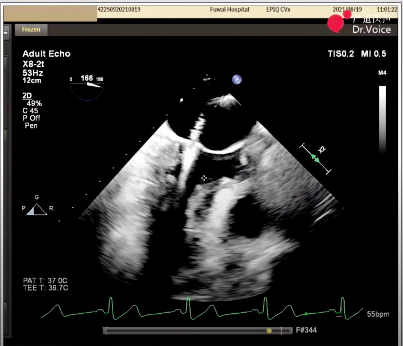

患者为71岁女性,因胸闷气喘6个月入院。术前经胸超声检查提示二尖瓣重度反流(MR4+),前叶脱垂、腱索断裂,EF 74%,LA 45mm、LVEDV 46mm。经食道超声检查可见A1区脱垂,腱索断裂,脱垂范围17mm,MVA 5.5cm²,瓣环29mm,前叶25mm,后叶10mm。

二尖瓣夹释放后,超声显示反流几近消失,二尖瓣前向峰值流速1.2m/s,平均跨瓣压差3mmHg。患者各项生理指标正常,手术顺利完成,手术操作耗时约120 min。

术后生命体征及超声效果